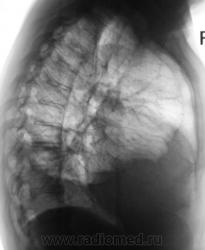

Множественные осумкования в правой плевральной полости жидкости и газа - эмпиема.

Из очевидного - частично осумкованный правосторонний гидроторакс. Неясно, почему правое легкое как бы поддавливает правый контур срединной тени. Нарушение бронхиальной проходимости, клапанная эмфизема? Пациент нуждается в дообследовании.

Конечно же посмотрел бы пациента на УЗД. Больше данных за эмпиему правой плевральной полости.